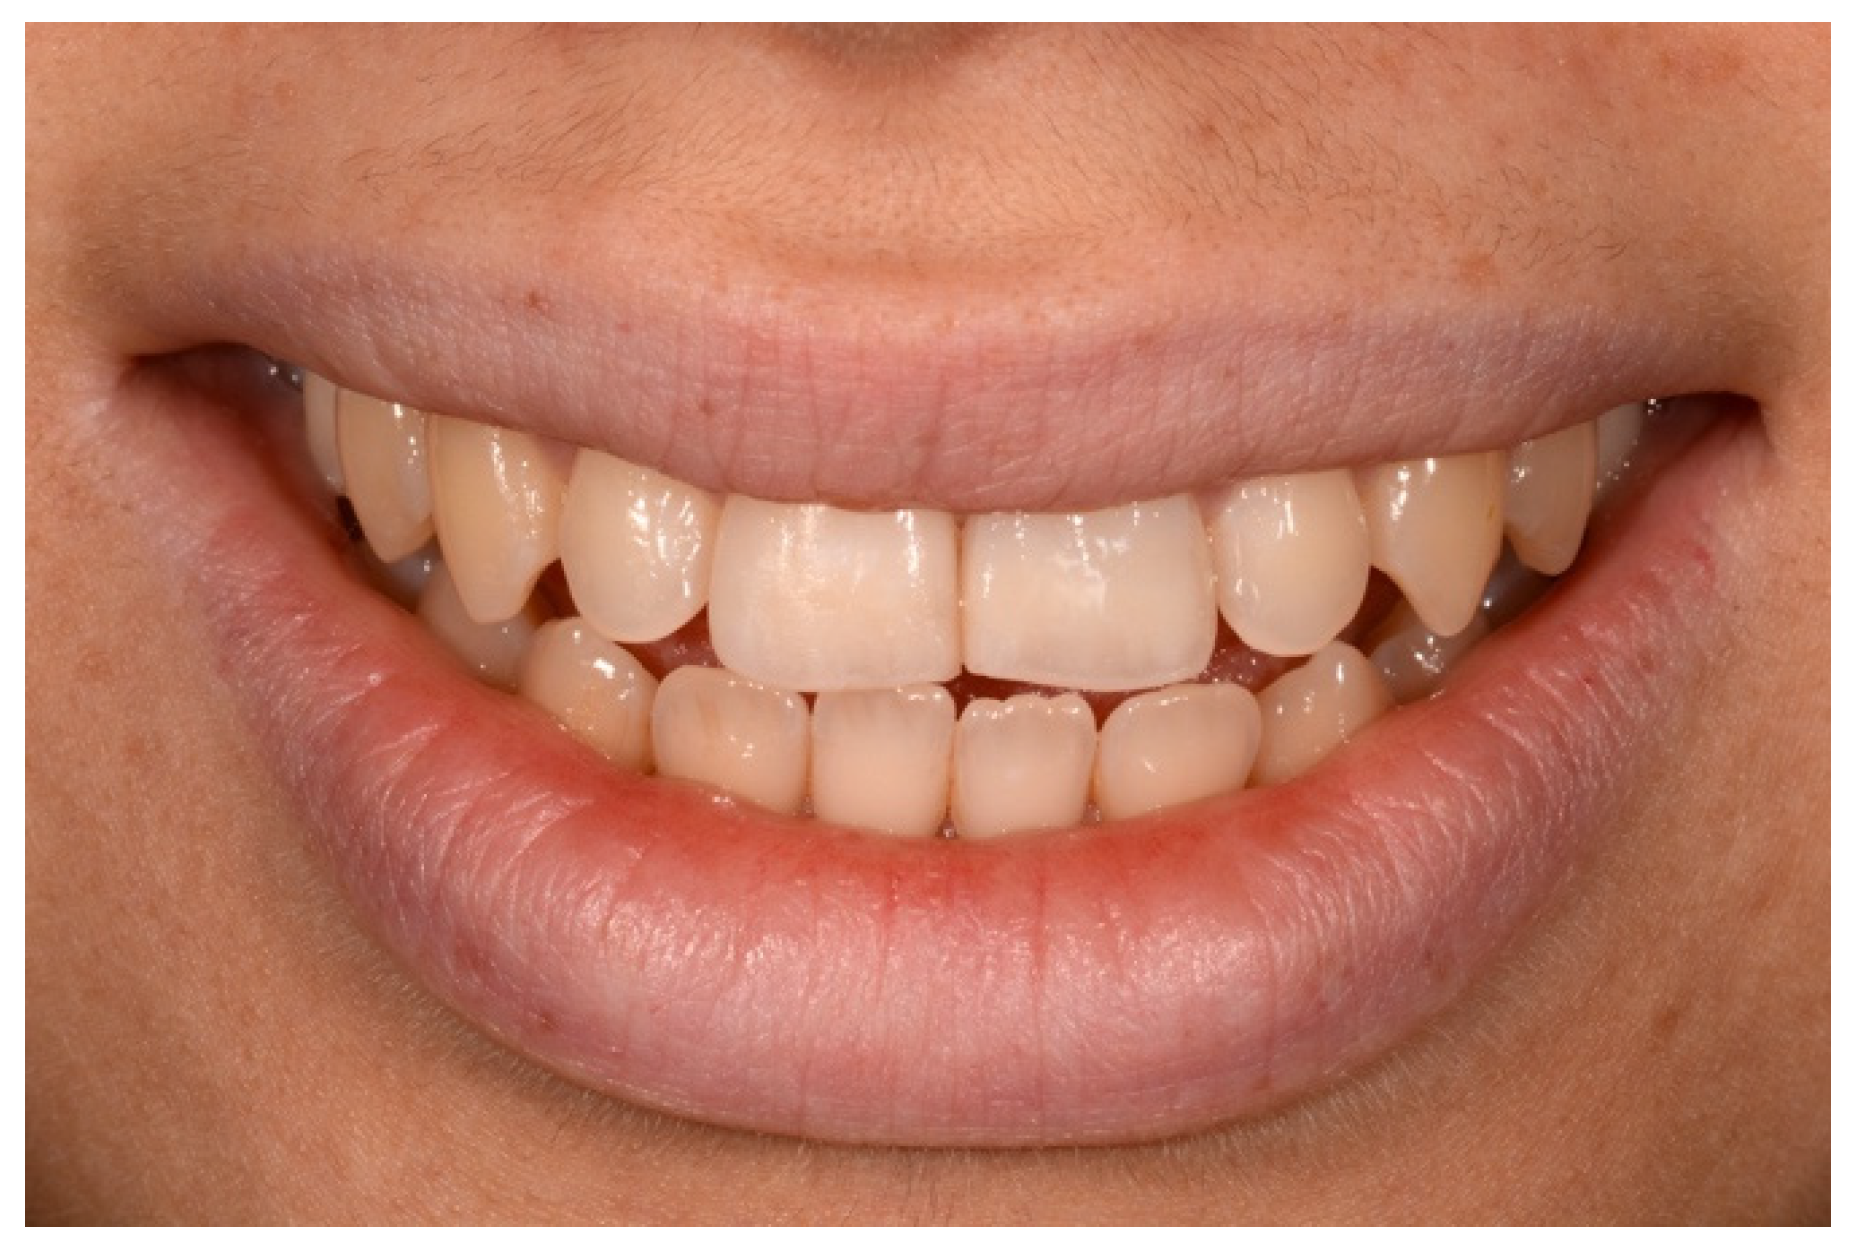

2. Case Presentation